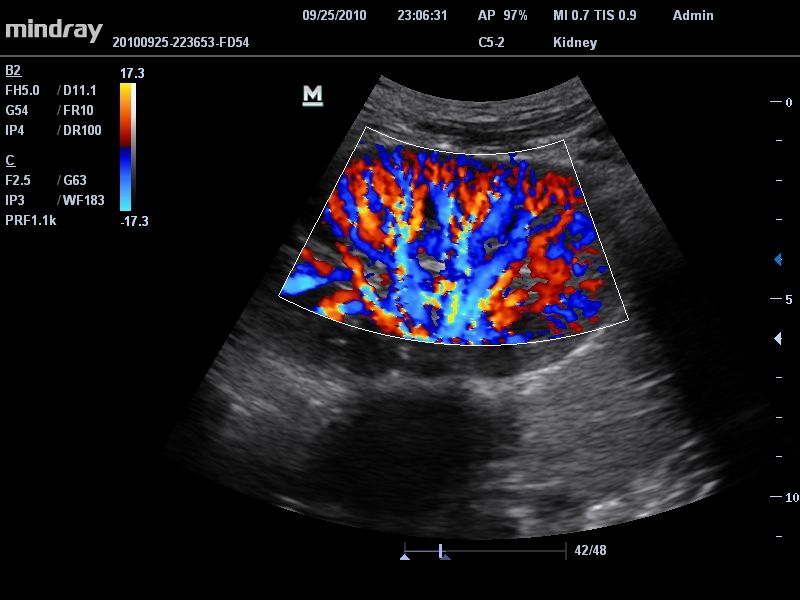

Цветовой допплер:

Да

Энергетический допплер:

• Режимы сканирования: B/M/CFM/PDI/Направленный PDI/PW, HPRF, Тканевая гармоника, М- и цветной М-режим.

• Формирование восьмиугольного пучка: обеспечивает баланс между временным разрешением и разрешением сканирования.